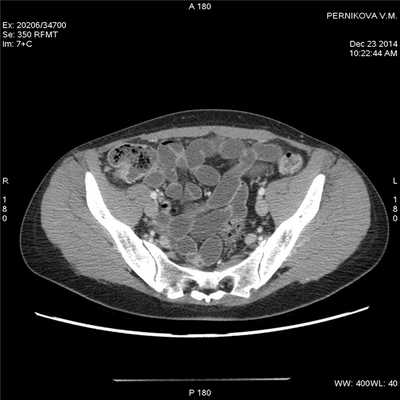

(Справа) На КТ у этого же пациента определяется большее количество растянутых петель тонкой кишки, слизистая оболочка которых интенсивно накапливает контраст на фоне подслизистого отека. Визуализируются также группы умеренно увеличенных лимфатических узлов брыжейки (Слева) На КТ у этого же пациента визуализируются два сегмента воспаленной тонкой кишки, разделенные неизмененными участками - классические «прерывистые» поражения при болезни Крона. Обратите внимание на полнокровные прямые сосуды, кровоснабжающие более дистальные отделы воспаленного кишечника.

(Справа) На КТ у этого же пациента визуализируются другие сегменты воспаленного кишечника с контрастным усилением слизистой оболочки, утолщением стенки и сужением просвета. (Слева) На реформатированной корональной КТ у этого же пациента визуализируются отдельные сегменты воспаленной кишки наряду с брыжеечной лимфаденопатией и выбухающими кровеносными сосудами.

(Справа) На корональной КТ у этого же пациента визуализируются воспаленные сегменты кишечника определяется также брыжеечная лимфаденопатия. Диагноз болезни Крона был подтвержден при колоноскопии и биопсии терминальных отделов подвздошной кишки.